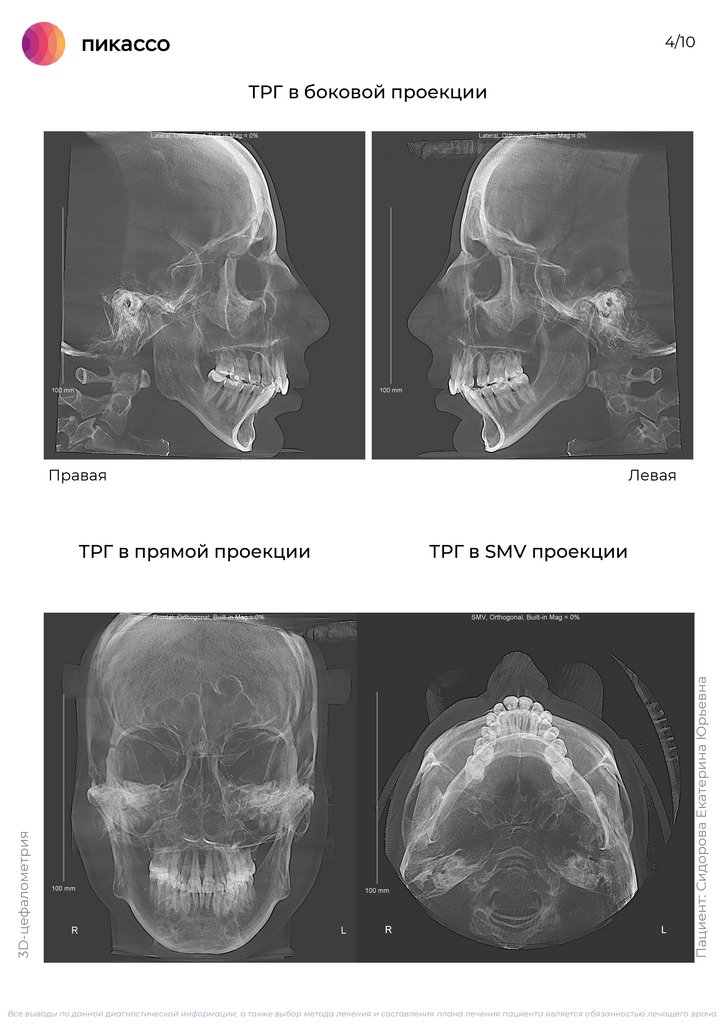

5.

4/10

ТРГ в боковой проекции

Правая

ТРГ в SMV проекции

Пациент: Сидорова Екатерина Юрьевна

3D-цефалометрия

ТРГ в прямой проекции

Левая

Все выводы по данной диагностической информации, а также выбор метода лечения и составления плана лечения пациента является обязанностью лечащего врача.